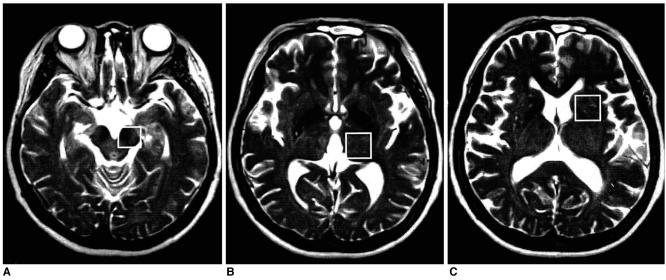

Fifteen patients each underwent stereotactic thalamotomy for the control of medically refractory parkinsonian tremor. Single-voxel 1H MRS was performed on a 1.5T unit using a STEAM sequence (TR/TM/TE, 2000/14/20 msec), and spectra were obtained from substantia nigra, thalamus and putamen areas, with volumes of interest of 7-8 ml, before and after thalamotomy. NAA/Cho, NAA/Cr and Cho/Cr metabolite ratios were calculated from relative peak area measurements, and any changes were recorded and assessed.

In the substantia nigra and thalamus, NAA/Cho ratios were generally low. In the substantia nigra of 80% of patients (12/15) who showed clinical improvement, decreased NAA/Cho ratios were observed in selected voxels after thalamic surgery (p < 0.05). In the thalamus of 67% of such patients (10/15), significant decreases were also noted (p < 0.05).